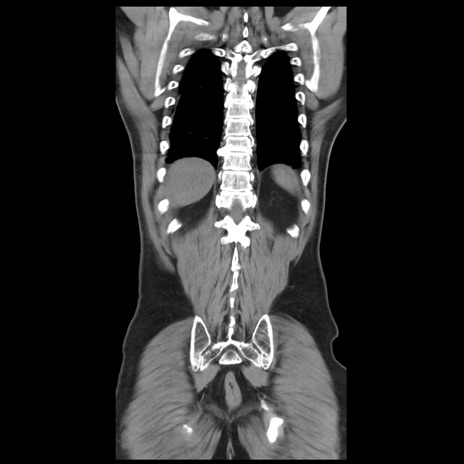

症例20(冠状断像)

【症例】 60歳代男性

【主訴】 腹部膨満、嘔吐

【現病歴】5日前頃より倦怠感を認め食事量減少し4日前の朝嘔吐、食事摂取困難となった。 3日前近医受診し点滴施行され整腸剤などを処方された。 当日他院を受診し、腹部膨満著明、炎症反応の上昇(CRP10.8、WBC11200)あり、紹介受診となる。

【身体所見】 意識JCS1 受け答えがはっきりしないBP 111/57mHg、 P 67bpm、、BT35.2°C、SpO2 97%(RA)、 腹部:膨隆、打診で鼓音あり、全体的に圧痛有り、腸蠕動音(-)、反跳痛ははっきりせず。

【データ】WBC 11400、CRP 14.20